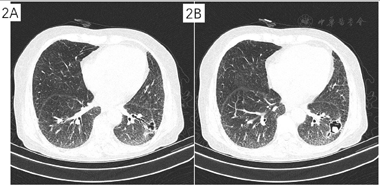

分别于2021年12月30日、2022年1月6日、2022年1月17日、2022年1月25日行4次支气管镜检查及治疗,超声探查示左下叶前基底段外侧支异常低回声,局部予乙酰半胱氨酸+生理盐水反复灌洗后,注射猪源纤维蛋白粘合剂+两性霉素B,术后咳嗽症状缓解出院。2022年3月11日于我院通州院区住院,3月12日胸部CT平扫(经支气管镜局部注药后复查),曲菌球较我院初诊缩小(图2)。于2022年3月21日行经皮穿刺注药(猪源纤维蛋白+两性霉素B),复查即刻CT示气胸,予胸腔闭式引流(图3)。2022年3月23日行微波消融治疗(图4),45 W消融3 min,复查CT示覆盖病灶,继续保留闭式引流,次日复查胸片无气胸,拔除引流管。

三、腔内注药为可选择的局部治疗策略。根据我院情况,考虑患者经皮操作出血风险,予4次气管镜下治疗,超声定位后予注药,注药策略选择猪源纤维蛋白粘合剂+两性霉素B混合物。其中猪源纤维蛋白粘合剂的作用主要为降低出血风险并使得两性霉素B缓释。两性霉素B是多烯类抗真菌药,抗真菌谱广而强,但是静脉给药时,常用治疗量所达到的药物浓度对真菌仅有抑菌作用[5]。欧洲临床微生物学与感染病学会(ESCMID)与欧洲呼吸病学会(ERS)于2015年发布的《慢性肺曲霉病诊断与治疗指南》对于局部注药剂量和溶液浓度的相关规定进行了说明[6],相关临床报道显示将抗真菌药物注入肺部空洞性病灶来缓解曲霉病灶有很好的临床效果[7]。患者经4次支气管注药复查提示曲霉球较我院初诊有缩小,为加强局部治疗效果,予经皮穿刺注药,药物选择同前。充分告知大出血风险,经皮穿刺操作时备床边支气管镜应对可能的大出血。患者最终手术过程顺利。